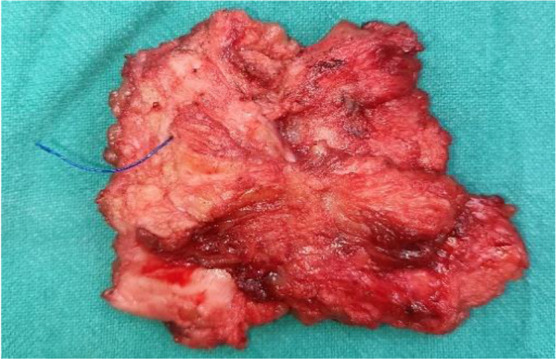

Case report: We report a case of a 26-year-old female presenting with painful swelling at a caesarean section scar, previously excised for similar complaints. Physical examination revealed a solid soft tissue mass on the scar. Magnetic resonance imaging (MRI) identified a 2x2 cm lesion in the right abdominal wall, suggestive of suture granuloma. Surgical excision revealed prolene suture material within the granulomatous tissue. Histopathology confirmed foreign body reaction.

Conclusion: Recurrence post-prior excision underscores the importance of complete granuloma removal. Differential diagnoses included scar endometriosis and inflammatory lesions. Suture granulomas, though rare, require consideration in scar-related swelling. Collaboration between specialties ensures accurate diagnosis and management.